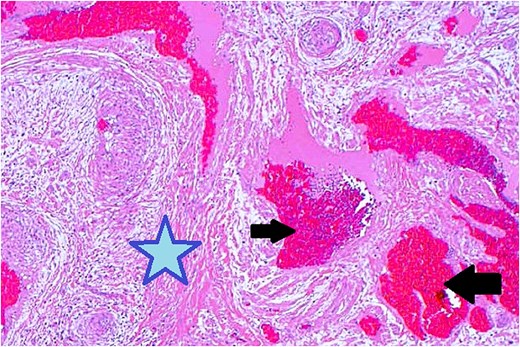

Surgical excision was performed via a subciliary approach, and the mass was removed entirely. Macroscopic examination revealed a 15 × 10 mm encapsulated tumor. Histology demonstrated interlacing bundles of smooth muscle cells surrounding thick-walled vascular channels without atypia, mitotic figures, or necrosis. Immunohistochemical staining was positive for smooth muscle actin (SMA) and desmin, confirming the smooth muscle origin of the tumor (Fig. 5).

Histopathological examination with hematoxylin and eosin staining shows muscular components (marked with a star) and vascular components (marked with arrows).